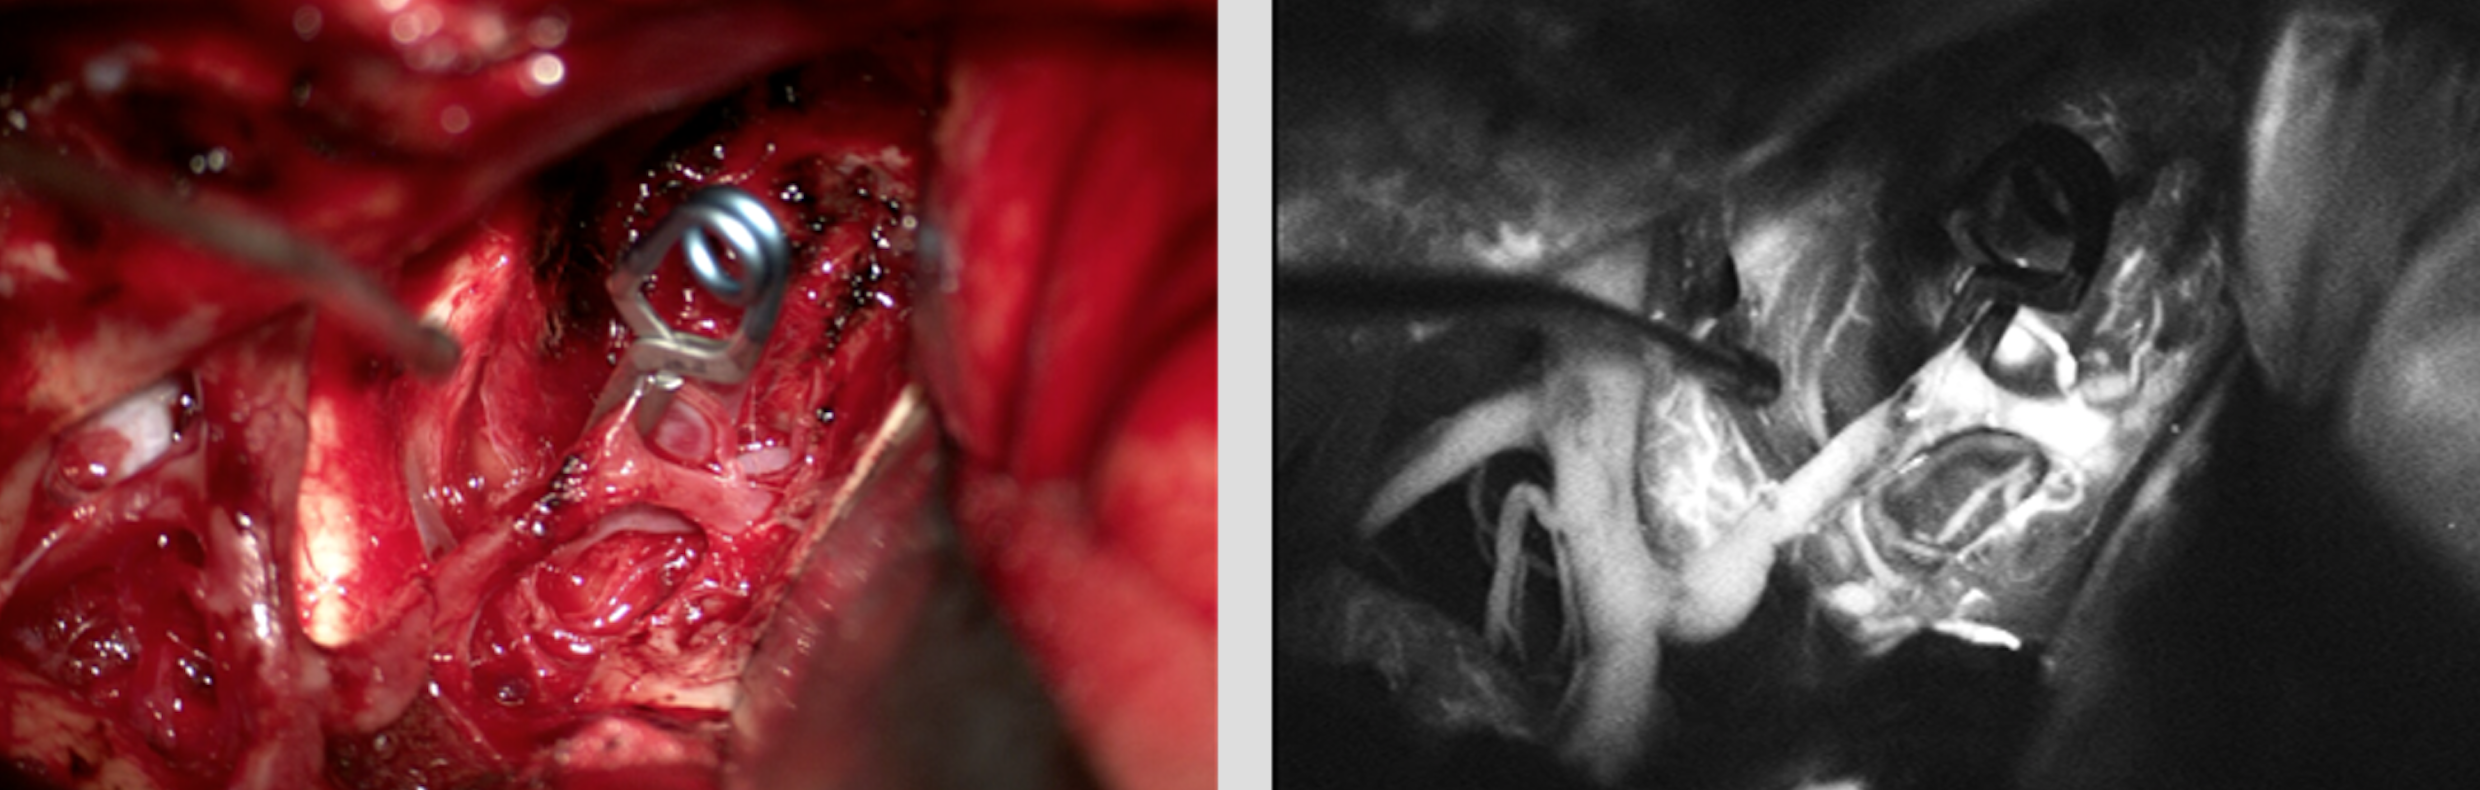

术中解剖

颅内动脉瘤的精准夹闭

术中荧光造影助力动脉瘤精准夹闭